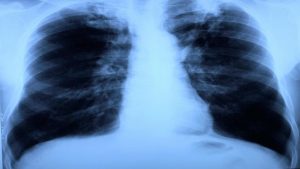

من المعروف أن مرض السل هو مرض تنفسي يصيب الرئتين وخاصة الحويصلات الهوائية، حيث تتم الإصابة بنوع معين من البكتيريا يطلق عليها مايكوبيكتريم فتحدث على الفور مجموعة من العوامل الالتهابية والمناعية بداخل الرئتين، مما يؤدي إلى حدوث تجاويف داخل الحويصلات الهوائية نتيجة انقسام ونمو بكتيريا الميكروبيكتيرم بداخلها، فينتج عن ذلك العديد من الأعراض التي سنتناولها بالذكر بداخل هذا المقال.